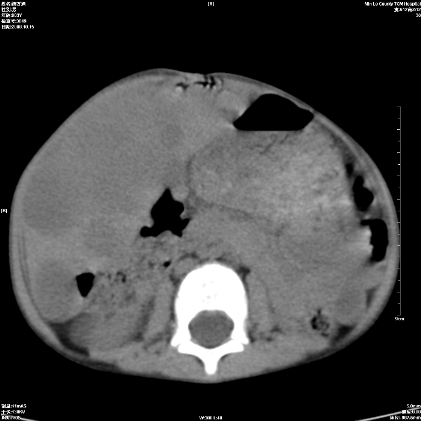

标题: PED1609:男性,3岁。彩超示肝Ca.

3岁;肝低密度灶;有钙化;有转移灶;考虑肝母细胞瘤;查afp

考虑:1、右侧后下纵隔畸胎瘤。

2、肝脏多发血管内皮细胞瘤。

建议:增强确诊。